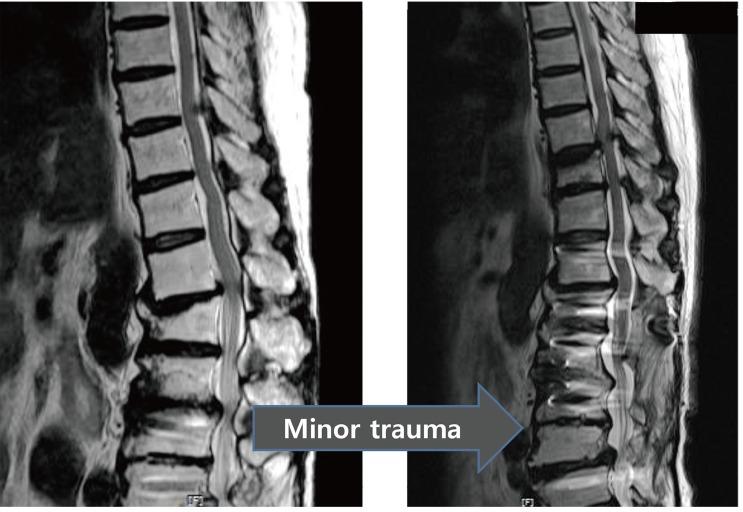

Ossification of the ligamentum flavum is a rare cause of thoracic myelopathy. It develops in East Asians more frequently than in people from other areas. The exact pathophysiology has not been elucidated yet; however, it largely depends on biomechanical alterations, especially changes in the tensile force. Because the spinal cord is compressed from the posterior side, the first and most common clinical manifestation is usually loss of functional gait and spastic paralysis, which develop as the spinal cord compression progresses. The choice of diagnostic imaging is T2 sagittal magnetic resonance imaging scanning. Whole spine scanning is mandatory to identify multiple areas of compression and any associated distal lumbar diseases. Fine computed tomography imaging is necessary to make a differential diagnosis and set up a precise surgical plan. Conservative treatment does not work in this disorder. Decompression surgery is the only option and prognosis after surgical treatment is better with this disorder than with other causes of thoracic myelopathy. The severity of preoperative symptoms and the time interval before surgical treatment are the most important prognostic factors.

黄韧带骨化是胸段脊髓病的罕见病因。东亚地区的发病率高于其他地区。确切的病理生理学尚未阐明;然而,其很大程度上取决于生物力学改变,尤其是张力变化。由于脊髓从后侧受到压迫,最初且最常见的临床表现通常是功能性步态丧失和痉挛性瘫痪,随着脊髓压迫的进展而出现。诊断性影像学检查选择T2矢状面磁共振成像扫描。必须进行全脊柱扫描以识别多个压迫部位以及任何相关的远端腰椎疾病。精细的计算机断层扫描成像对于进行鉴别诊断和制定精确的手术方案是必要的。保守治疗对这种疾病无效。减压手术是唯一的选择,并且与其他胸段脊髓病病因相比,这种疾病手术治疗后的预后更好。术前症状的严重程度和手术治疗前的时间间隔是最重要的预后因素。